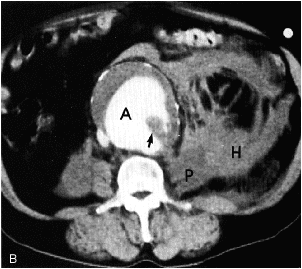

A=aortic aneurysm.

short black arrow=mural thrombus.

H=hyperdense

STREAKY SHAPED

hematoma related to psoas muscle(P).